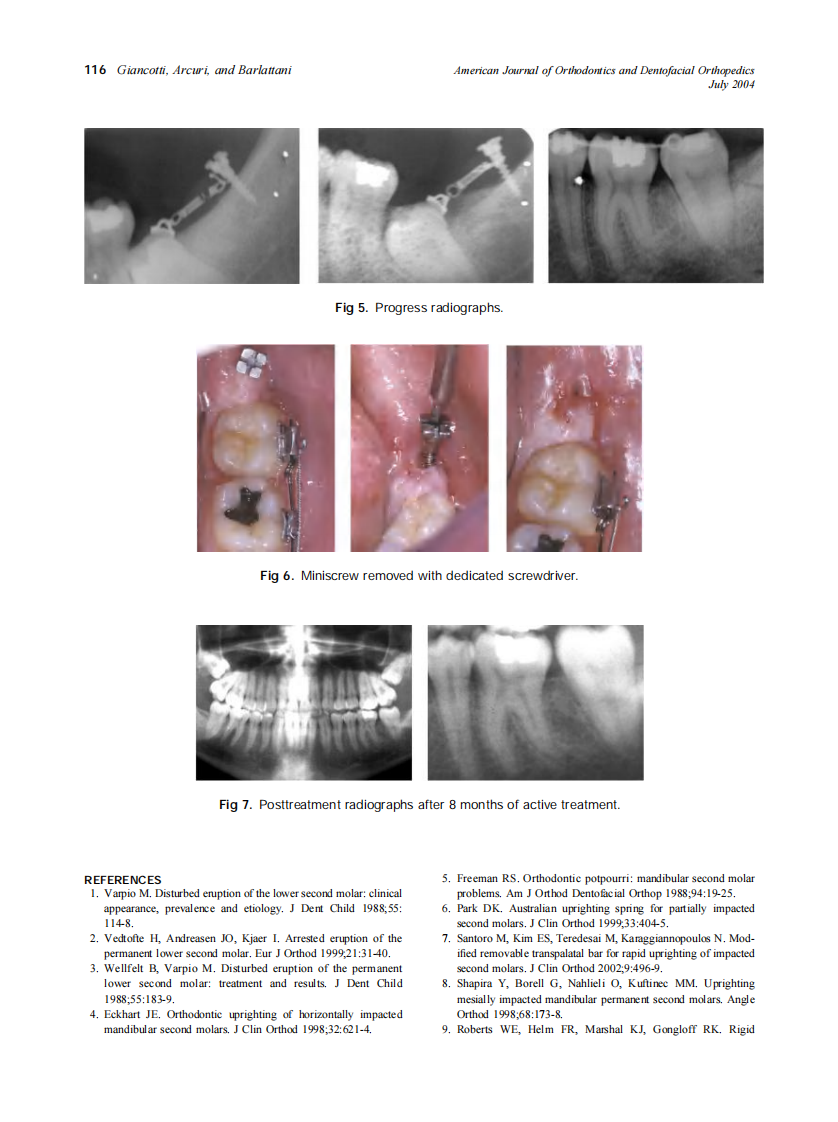

2004_126_1_113_117_Giancotti.pdf